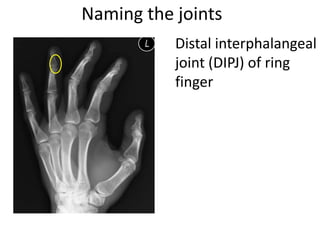

- Naming the bones, joints, tendons, nerves and skin landmarks of the hand and wrist.